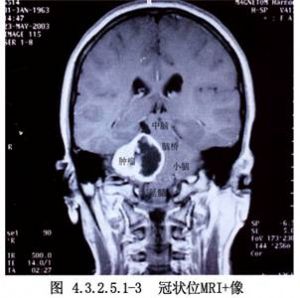

聽神經瘤影像表現見圖4.3.2.5.1-1~4.3.2.5.1-4。